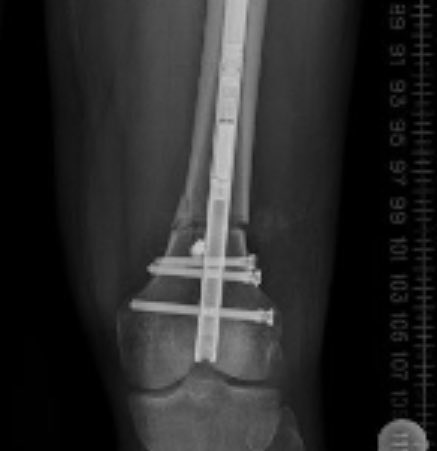

#Precice for#deformity correction and#LimbLengthening is catching on. Blocking screws have really made a difference in our success.pic.twitter.com/uWVS0LOlUQ